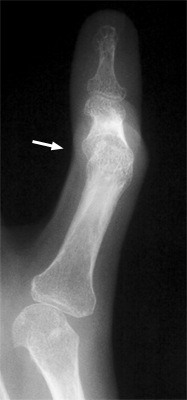

Among the many osseous abnormalities that may be seen in Rheumatoid Arthritis, the boutonniere deformity is the culmination of multiple abnormalities in the hand. Specifically, the deformity arises from hyperextension of the distal interphalangeal joint, while the proximal interphalangeal joint is flexed.